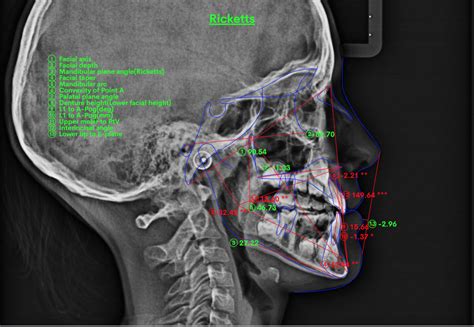

Análisis Cefalométrico

Puntos Cefalométricos Utilizados

Planos Utilizados

Mediciones Angulares

Mediciones Lineales

Descripción de las Mediciones Angulares Utilizadas